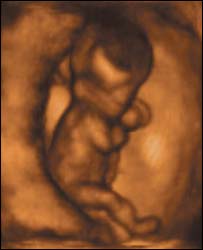

भ्रूण

नई मशीन गर्भस्थ शिशु की हलचलों की तस्वीरें लेता है

प्रोफ़ेसर कैम्पबेल ने जो मशीन तैयार की है वह न केवल त्रि-आयामी तस्वीर लेती है बल्कि उसे उसी समय रिकॉर्ड भी कर लेती है.

उनका कहना है कि उनकी मशीन से बच्चे के विकास के आरंभिक समय की गतिविधियों को देखा जा सकता है.

- 12 सप्ताह का भ्रूण अंगड़ाई लेता है और हाथ पैर चलाने लगता है, हालांकि तब तक माँ को बच्चे की गतिविधियों का पता नहीं चलता है.

- 18 सप्ताह का भ्रूण अपनी आँखें खोलने लगता है, अब तक डॉक्टर मानते थे कि भ्रूण जब तक 26 सप्ताह का नहीं हो जाता वह अपनी आँखें नहीं खोलता.

-26 सप्ताह का बच्चा किसी बच्चे की ही तरह हरकतें करने लगता है, मसलन वह मुस्कुराता है, रोता है, हिचकियाँ लेता है, खुजलाता है और अंगूठा चूसता है.